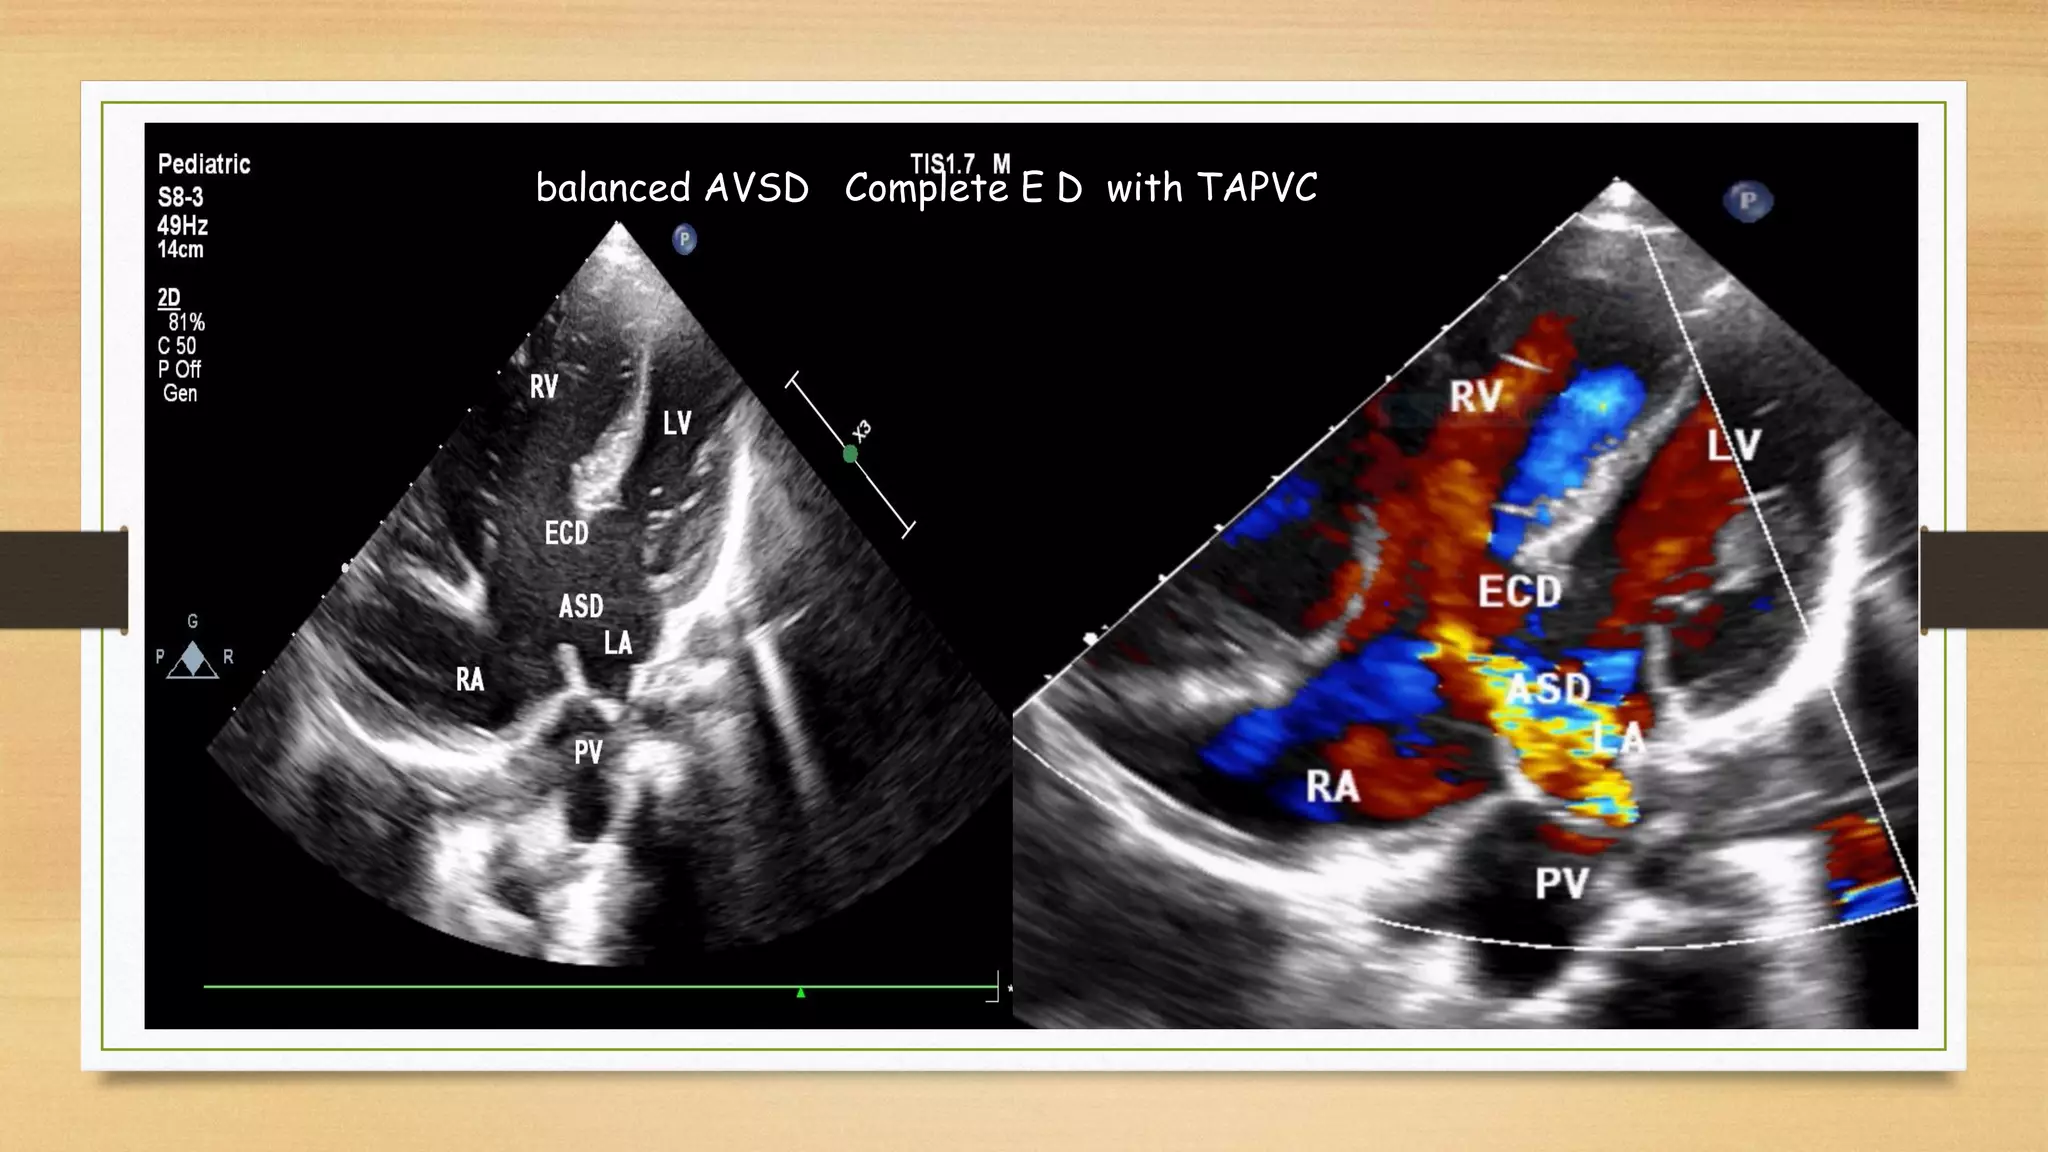

Balanced Complete A V S D

balanced AVSD Complete E D with TAPVC